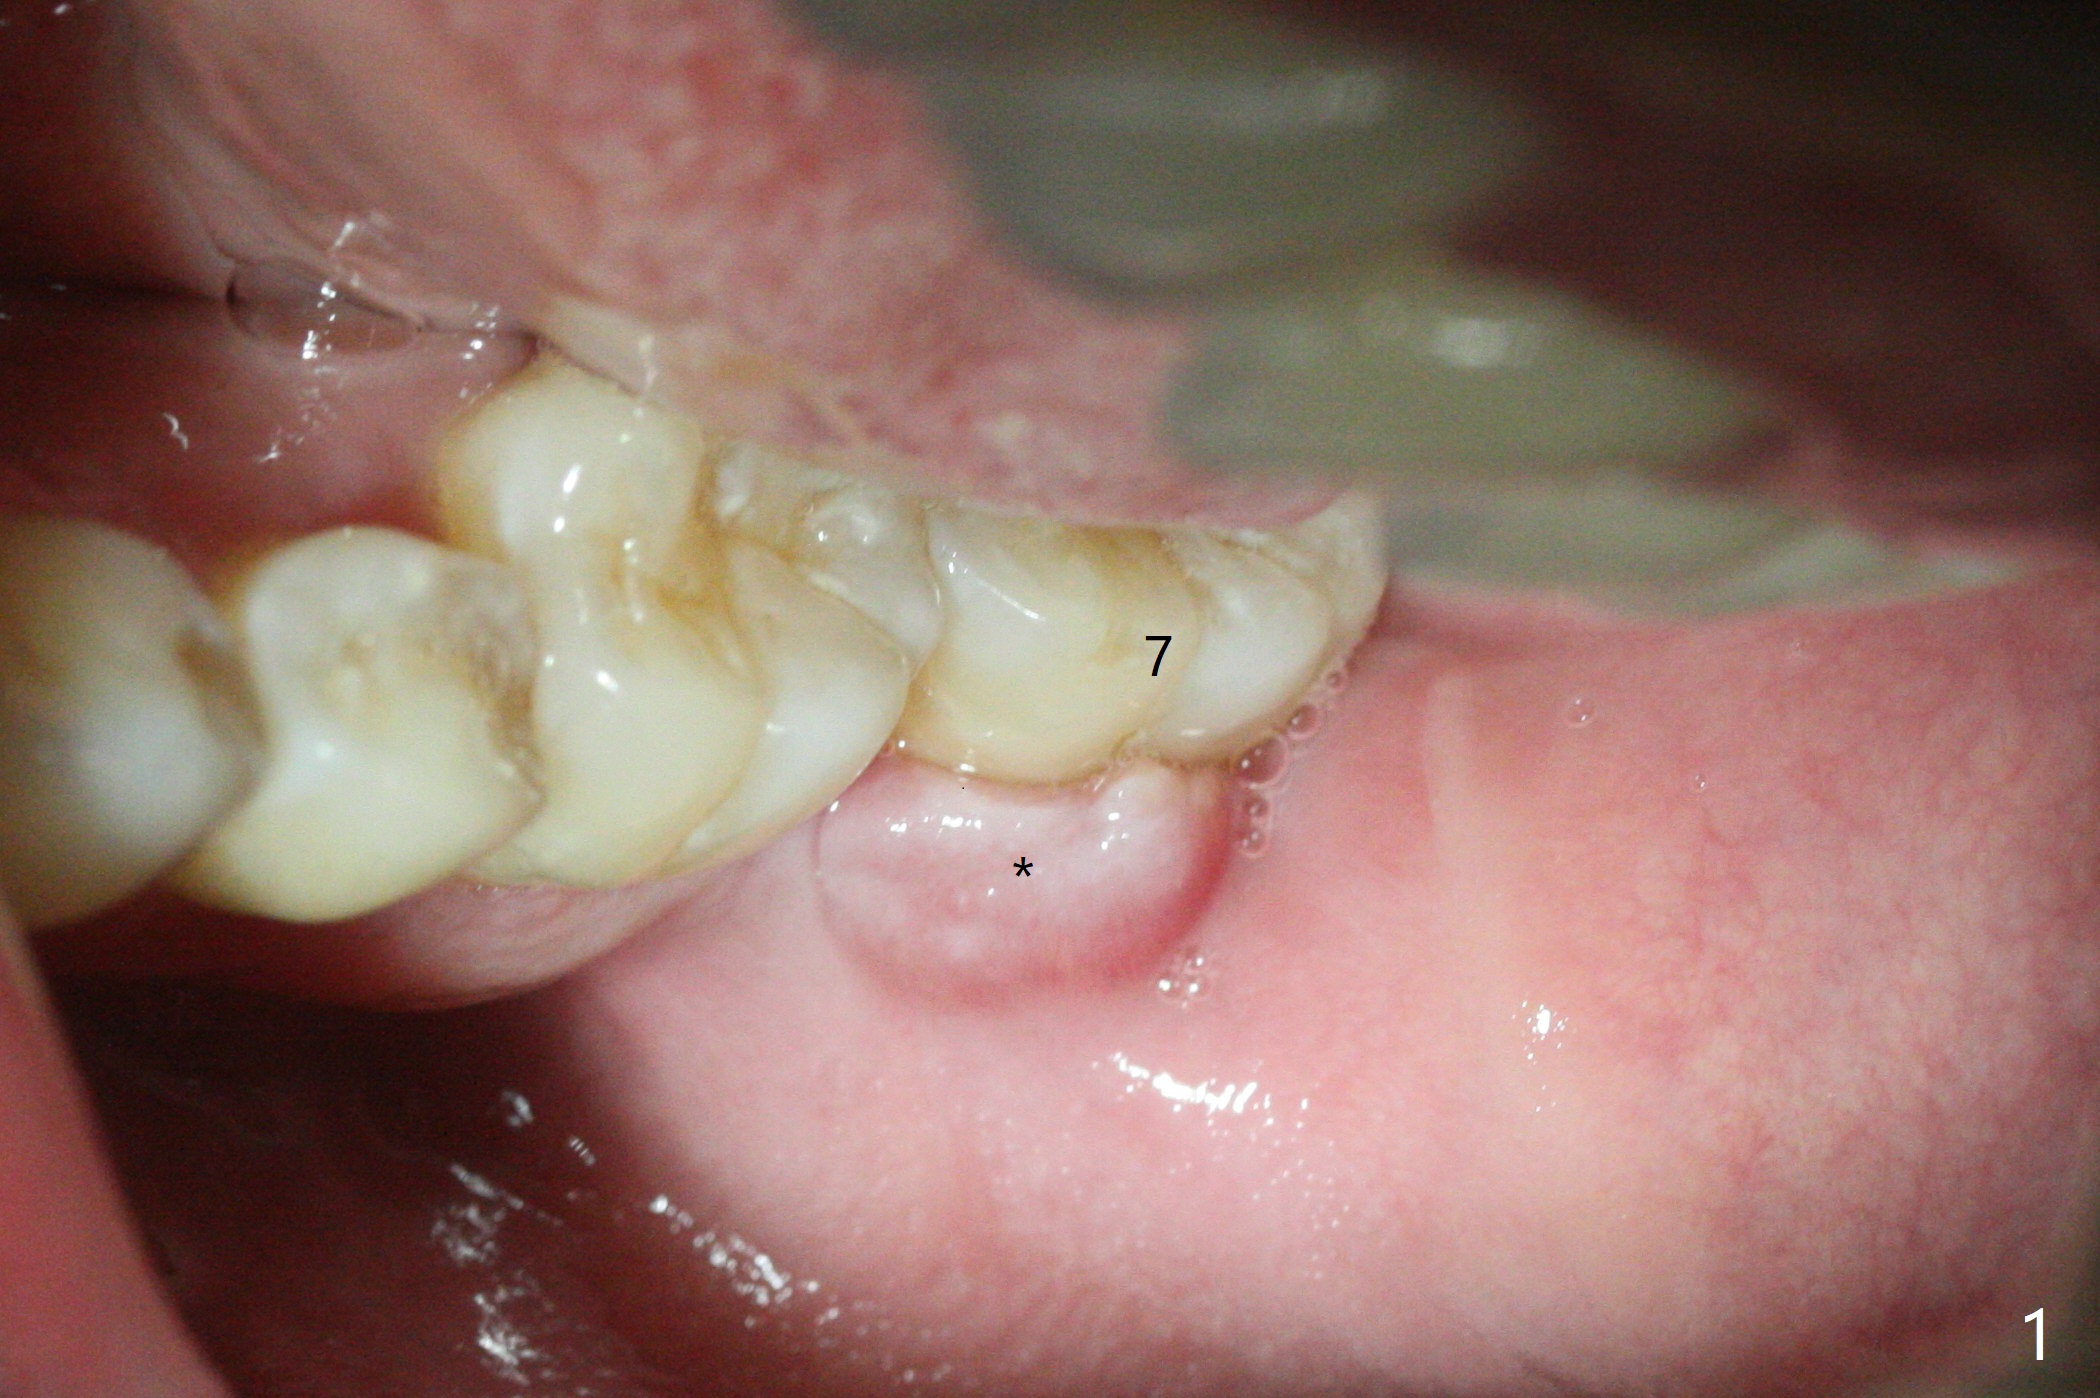

即刻种植即刻修复偶尔出现骨粉丧失,今天我们尝试临时基台,它可以制作像螺丝固位牙冠,可能会减少骨粉流失。左下7颊侧肿胀(图一:*),为了让植体(图二:绿色)植入中隔正中,钻洞时保留近中(M),远中(D)牙根。但是意想不到的是在导板指引下,钻头还是偏移近中(图三),而且颊侧(图四:圆圈),不过颊侧骨板没有缺损。由于牙根存在(硬),钻洞吃力,之后拔除,完成最后一个钻头,放置植体(图五),方位仿佛不错,临时基台(5.2x8(2)毫米)也完全就位,树脂围绕基台制作临时牙冠(图六),最后使用螺丝固位(*),颊侧肿胀牙龈必须用缝线固定(<),减少骨粉损失。由于牙冠与基台连接不好,病人汇报有些骨粉丢失。术后一个月检查尚可愈合正常,病人满意,已经做好思想准备做右下第二磨牙种植。临时牙冠进行修整。术后即刻近中牙槽窝间隙由粘性骨粉充填(图五),四个月后间隙消失(硬骨板也消失,图七),5.2x5(3)毫米粘固基台似乎没有完全就位,可能因为远中牙槽嵴阻挡(图七:*)。小一号基台仿佛完全就位(图八(咬翼片);图七(根尖片,可能失真)),但是临床上没有听到清脆声音(可能软硬组织阻挡)。随着时间推移,远中牙槽嵴吸收,当松动基台螺丝再次拧紧,可能会真正完全就位,必须拍摄完美咬翼片证实。这种植体芯(body, not threads)特别厚内部结构看不清楚。两周后粘固牙冠,然后取出牙冠和基台,清除残余粘固剂,然后复位,拧紧30Ncm。